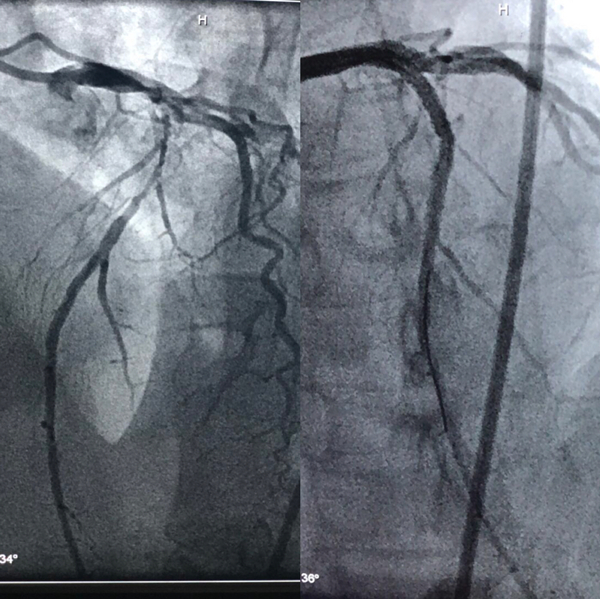

67岁的尹女士两年来反复发作胸闷、胸痛、气短,口服药物症状不能缓解。为求进一步诊治来我院急诊行CAG(冠状动脉造影术)检查,结果提示为:左冠脉走形区内可见明显钙化影。心脏血管左前降支近中段呈90%节段性狭窄,左回旋支近段狭窄90%局限性狭窄,中段后次全闭塞。右冠脉中段50-60%弥漫性不规则狭窄,其中以前降支钙化最为严重。心血管病院郑强荪院长评估患者病情后发现心脏血管确实钙化严重,在狭窄病变处植入支架有一定的难度,决定先为尹女士施行冠脉旋磨治疗,打通血管后再完成支架植入。

5月7日下午,由邓捷主任医师、薛嘉虹副主任医师、万招飞主治医师、李青主治医师、张荣主管护师、段文娜护师组成的冠脉介入治疗团队为尹女士采用全新的冠状动脉旋磨术。在完善相关术前检查后,邓捷主任医师用娴熟的技术术中先为血管打通一个“隧道”,使用带有超高速旋转头的转头将冠脉钙化斑块碾磨成细小的微粒,将血管腔内的斑块消除。经过几次旋磨后,阻塞血管腔的钙化斑块被逐渐消除,被磨成极其微小的颗粒,随血液循环至血管远端并通过毛细血管床吸收,之后完成冠状动脉支架置入手术。植入支架后为其行冠状动脉血管内超声发现血管狭窄解除,效果显著。